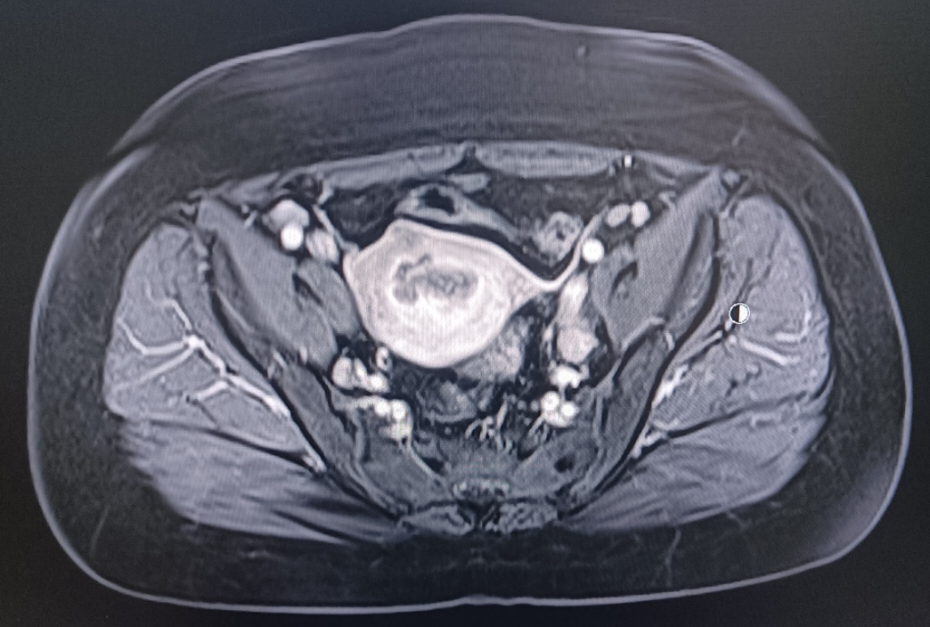

患者57岁,体重75千克,身高157厘米,血压147/100mmHg,绝经3年,阴道流血水样分泌物3个月,淋漓不尽,自服抗生素治疗无效就医。当地医院行妇科彩超检查发现子宫内膜厚约13毫米,宫内节育器位置正常,给予取环+诊断性刮宫,术后病理组织学检查报告提示:低分化癌,建议免疫组化标记明确类型。随就诊我院。

MRI:

术前诊断:子宫内膜癌(低分化)

术后诊断:子宫内膜样低分化腺癌(IIIC1)(微卫星稳定型)